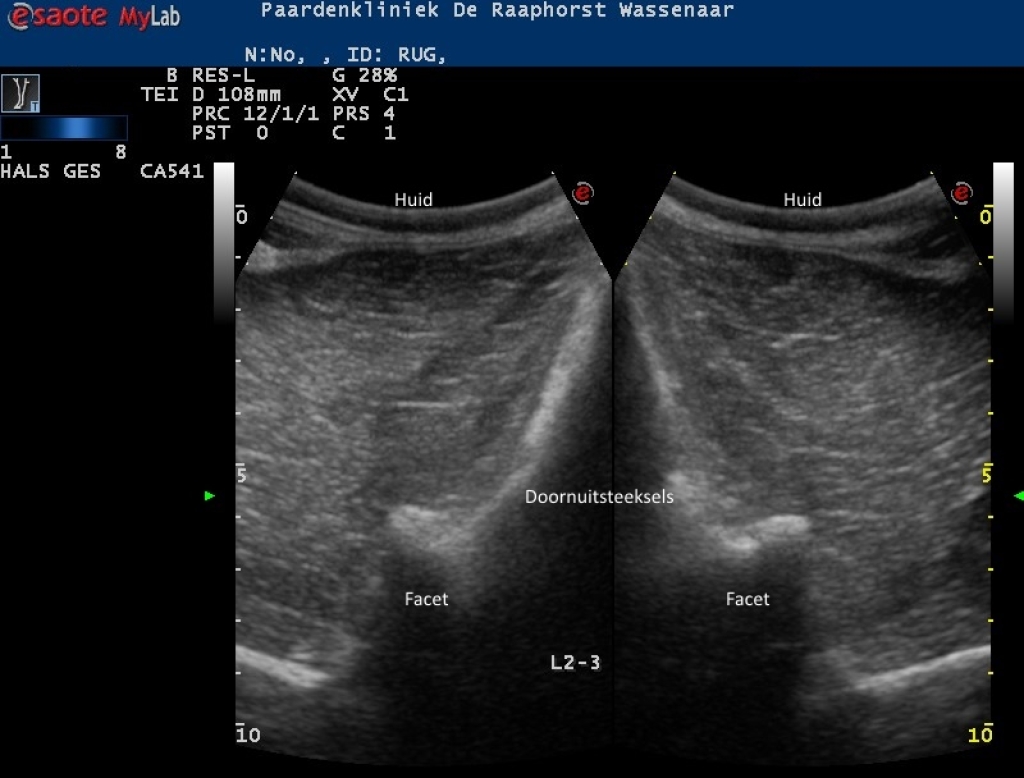

Links: Echobeeld van een licht artrotisch facetgewricht (links) op de thoracolumbale overgang

Rechts: Echobeeld van artrose van een facetgewricht in het lendengebied

Echobeeld van een licht artrotisch facetgewricht (links) op de thoracolumbale overgang

Echobeeld van artrose van een facetgewricht in het lendengebied